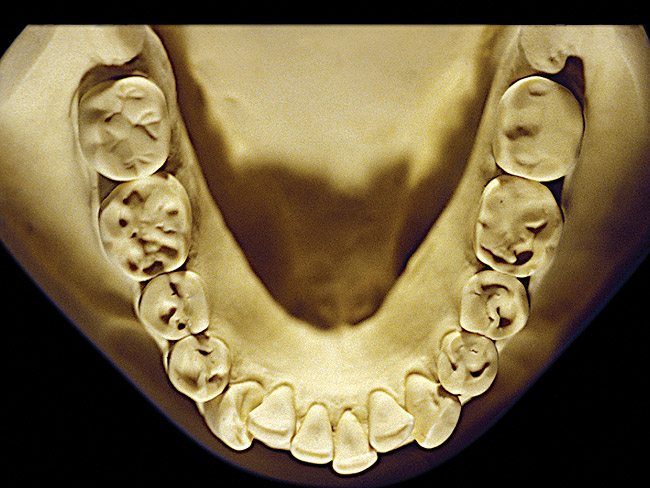

The patient shown in Figure 3 and Figure 4 exhibited severe NCLTS from bruxism. Examination of the casts indicated that the NCLTS was progressively greater toward the anterior teeth. Cupping and cratering was not present because there was no secondary cause. Figure 5 and Figure 6 detail another bruxism patient, but to a lesser degree and one with cupping/cratering caused by toothpaste. The cups or craters were not caused from bruxism because the teeth could not touch the bottom of the invaginations. In both featured patients, upon hand-articulating the casts, the NCLTS facets matched up and the diagnosis of bruxism was confirmed.

Figure 6  Moderate NCLTS from bruxism, mandibular arch.

Figure 6